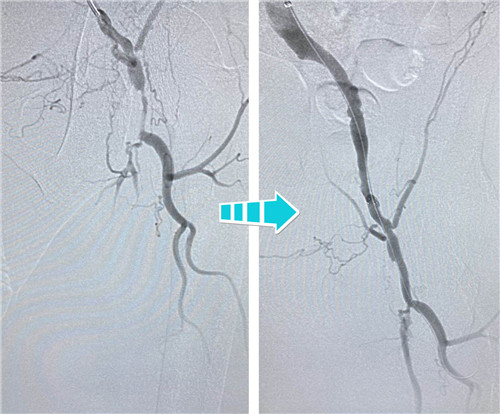

身經(jīng)百戰(zhàn)的放射科介入團(tuán)隊(duì),在南京鼓樓醫(yī)院血管外科王煒教授的指導(dǎo)下,決定為吳老先生行兩側(cè)髂血管成形術(shù)。手術(shù)當(dāng)天,選擇經(jīng)左側(cè)肱動脈入路,置入90CM長鞘,在導(dǎo)絲指引下,小心翼翼地通過左側(cè)股總動脈狹窄段,給予球囊擴(kuò)張,精確定位并植入支架,左側(cè)髂血管就此打通??紤]后期患者情況改善,可能還需要處理股淺動脈,專家們還預(yù)保留了股淺和股深開口。

右側(cè)完全閉塞的髂血管順行開通無果,但這也難不倒我們經(jīng)驗(yàn)豐富的鼓醫(yī)和石醫(yī)介入專家們,當(dāng)即決定由“順穿”改行“逆穿”。逆穿導(dǎo)絲難度大,技術(shù)要求高,十分考驗(yàn)術(shù)者的操作手法和預(yù)判,專家團(tuán)隊(duì)經(jīng)過內(nèi)膜下破膜逆行,一次性準(zhǔn)確對吻成功,同樣擴(kuò)張球囊、植入支架,血流瞬間恢復(fù)暢通。